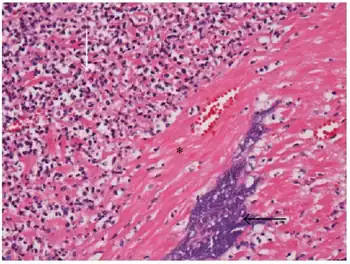

F. necrophorum is the cause of necrotic laryngitis ("calf diphtheria")[15] and liver abscesses[16] in cattle.